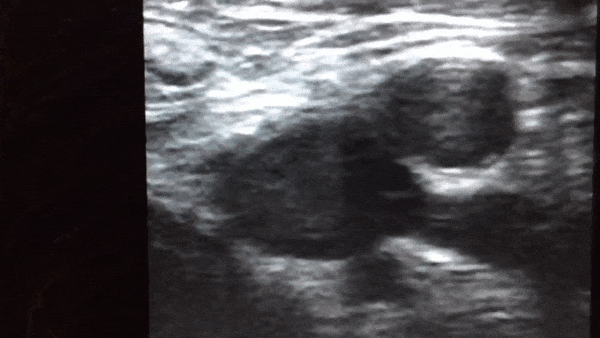

Surgical POCUS Certification Course This is an intensive, 2.5-day immersion course specifically designed for surgeons seeking rapid mastery of high-yield Point of Care Ultrasound (POCUS) skills. The curriculum emphasizes extensive "probe-in-hand" practice using standardized patients and is built to meet the rigorous standards for the Canadian Point Of Care Ultrasound Society (CPoCUS) Diagnostic Track Independent Practitioner (IP) certification. Participants will gain the confidence and technical proficiency to use POCUS as a critical diagnostic adjunct in acute care and surgical settings. Core Learning Modules The course focuses on four critical diagnostic examinations: 1. Hepatobiliary Assessment (Gallbladder): Participants will master visualizing the gallbladder to identify gallstones and recognize the specific signs of acute cholecystitis (wall thickening, fluid, sonographic Murphy's sign). 2. Abdominal Aorta / AAA Assessment: Focus on the accurate measurement of the abdominal aorta and the confident identification of an Abdominal Aortic Aneurysm (AAA), including recognizing surrounding free fluid indicative of potential rupture. 3. Renal & Bladder Assessment: Training includes detecting hydronephrosis to rule out obstruction, visualizing renal and bladder calculi, and accurately assessing bladder volume to diagnose urinary retention. 4. Vascular Assessment (DVT): Mastery of the comprehensive compression exam on the lower, proximal limb to effectively rule in/rule out Deep Vein Thrombosis (DVT), aiding in the assessment of pulmonary embolism risk. The Immediate Surgical Advantage Integrating these modules provides surgeons with rapid diagnostic certainty, reducing reliance on external services and streamlining patient management: - Emergency Triage & Shock: E.g Rapidly confirm/rule out AAA in undifferentiated Shock OR instantly differentiate biliary colic from acute cholecystitis - Post Op complications: E.g Quickly assess Oliguria to determine etiology (obstruction, retention or renal failure) OR screen for DVT before discharge. - Improve clinical diagnostic accuracy and decision making at the bedside.